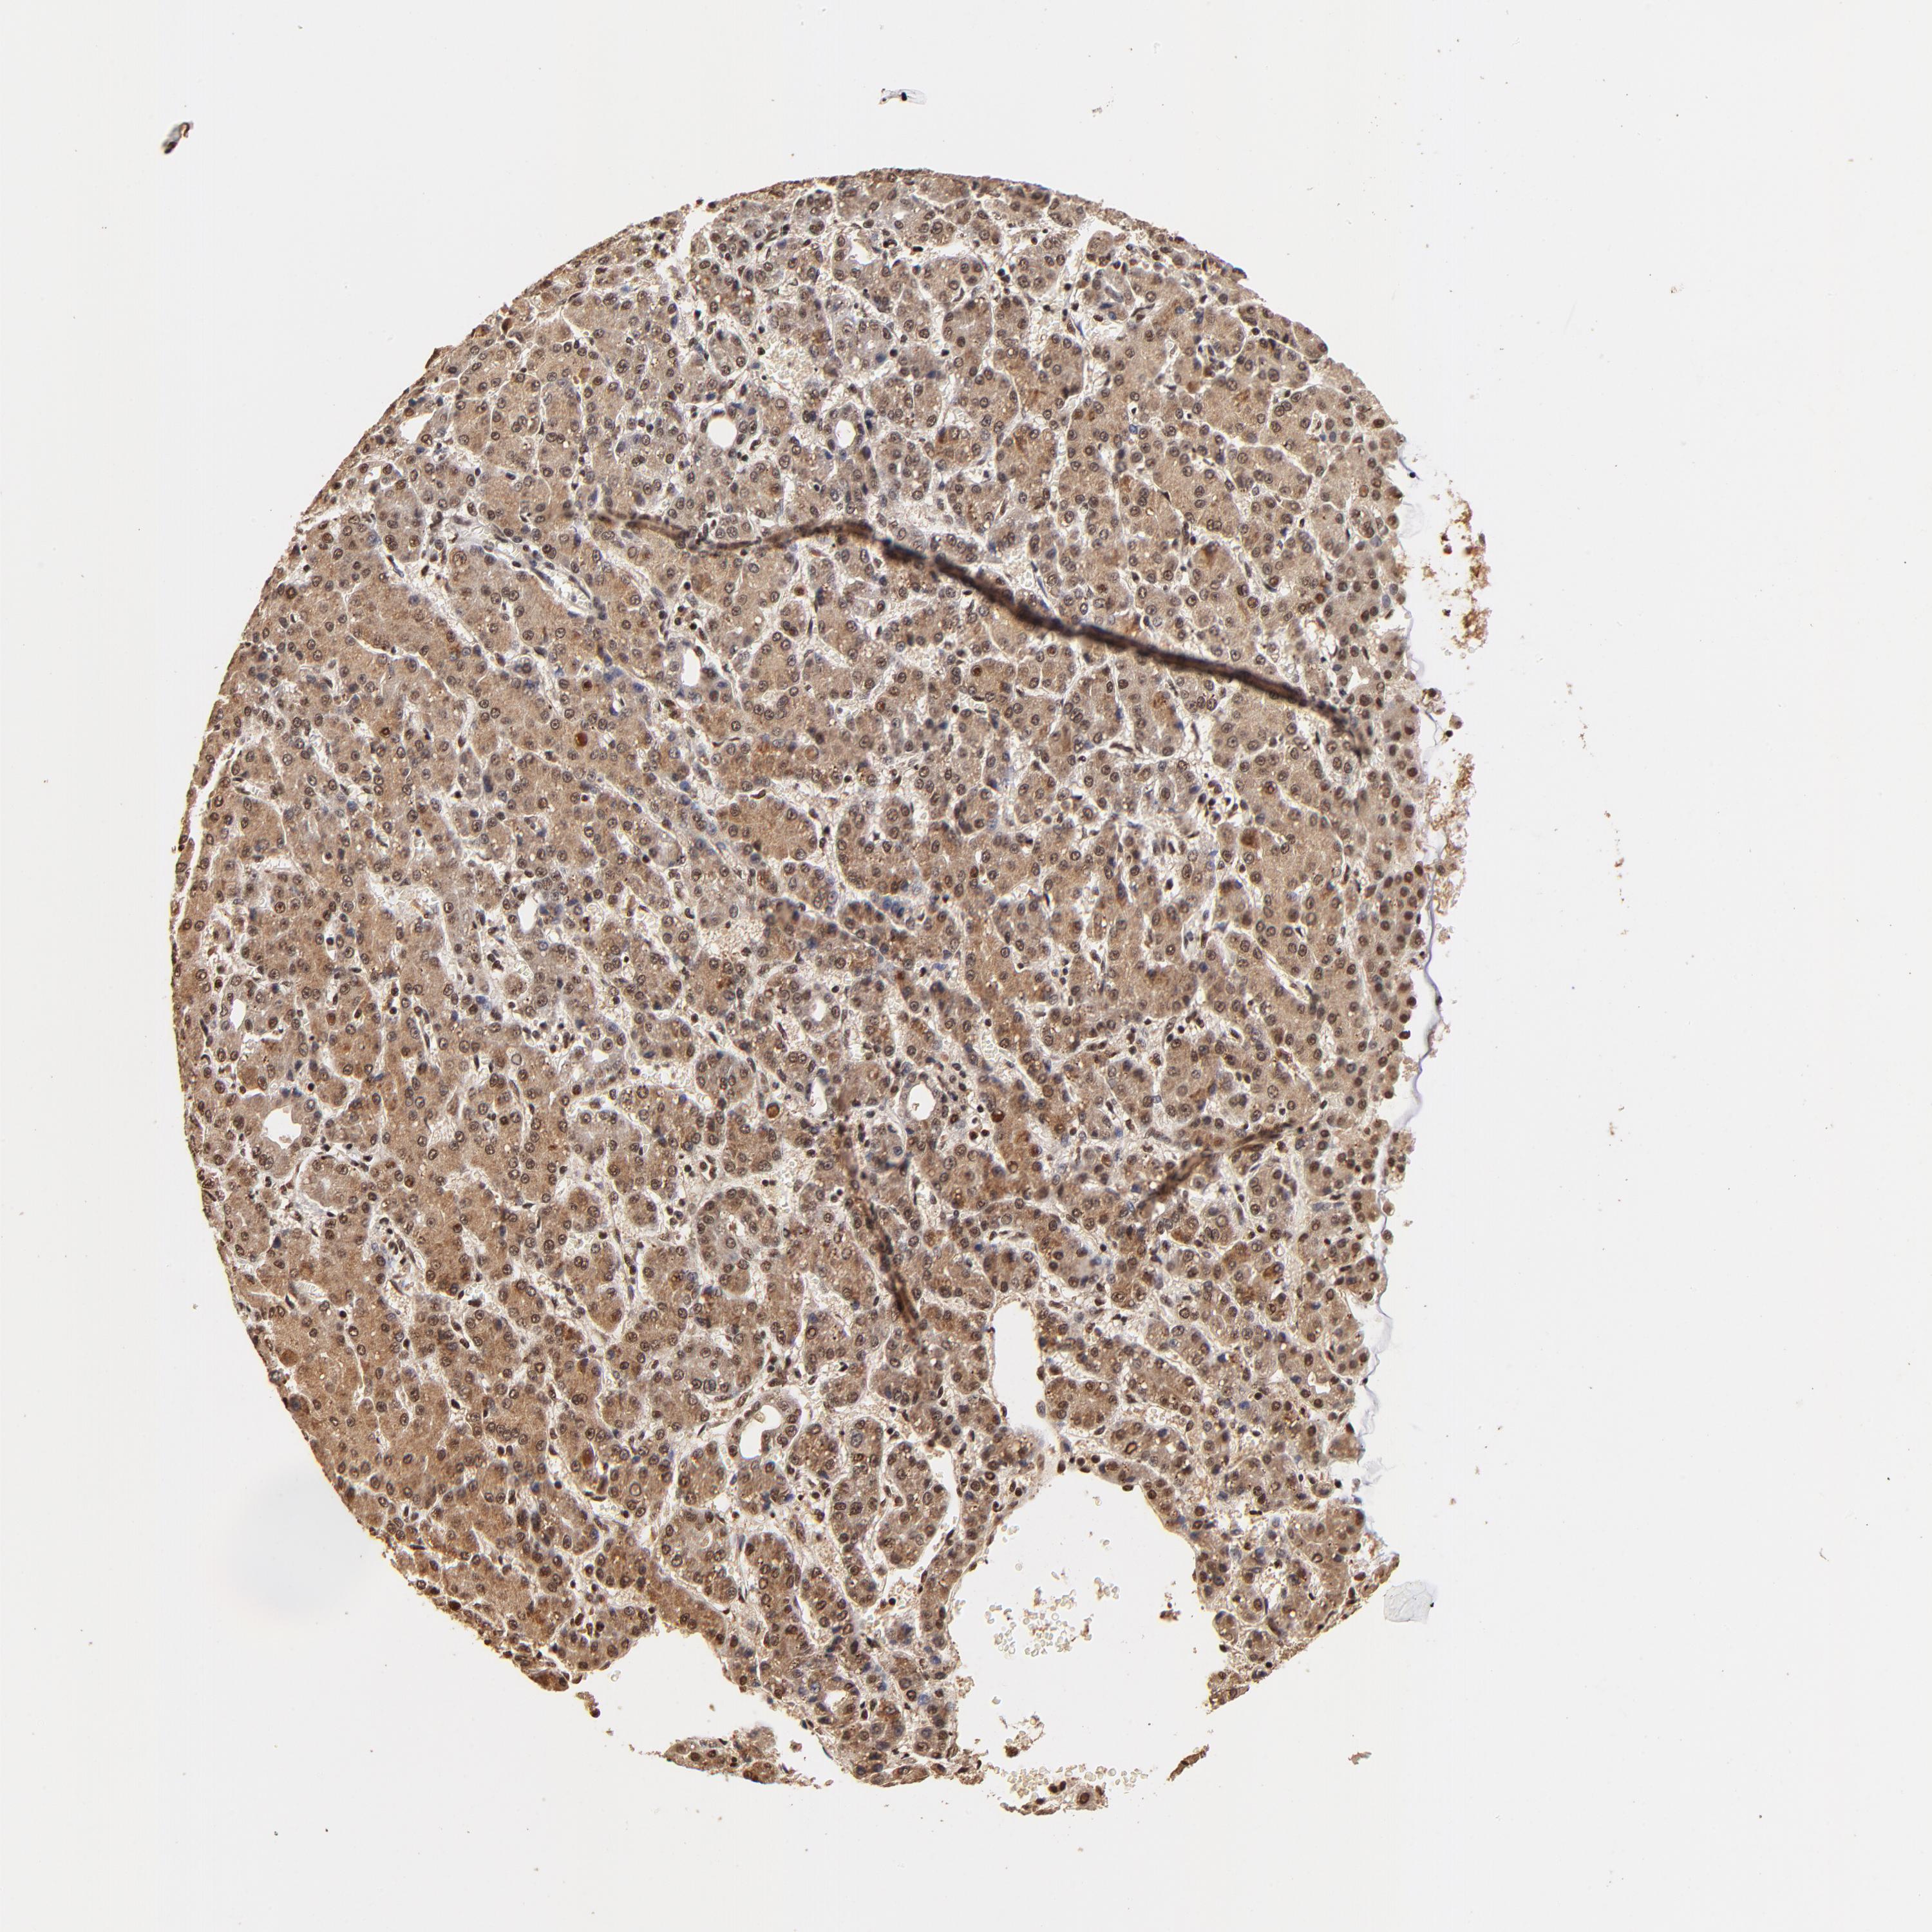

LIVER CANCER - Protein expressioni

A mouse-over function shows sample information and annotation data. Click on an image to view it in a full screen mode. Samples can be filtered based on level of antibody staining by selecting one or several of the following categories: high, medium, low and not detected. The assay and annotation is described here.

Note that samples used for immunohistochemistry by the Human Protein Atlas do not correspond to samples in the TCGA dataset.

Antibody stainingi

Antibody staining in the annotated cell types in the current human tissue is reported as not detected, low, medium, or high, based on conventional immunohistochemistry profiling in selected tissues. This score is based on the combination of the staining intensity and fraction of stained cells.

Each image is clickable and will lead to virtual microscopy that enables deeper exploration of all samples and also displays staining intensity scores, fraction scores and subcellular localization as well as patient and tissue information for each sample.

Antibody HPA003184

Antibody HPA003185

Staining

High

Medium

Low

Not detected

Intensity

Strong

Moderate

Weak

Negative

Quantity

>75%

75%-25%

<25%

None

Location

Nuclear

Cytoplasmic/membranous

Cytoplasmic/membranous,nuclear

Carcinoma, Hepatocellular, NOS

Cholangiocarcinoma